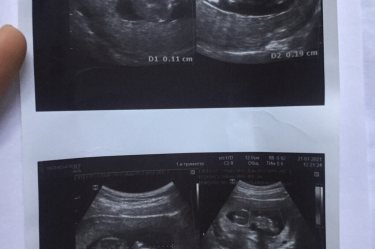

14 недель 💛